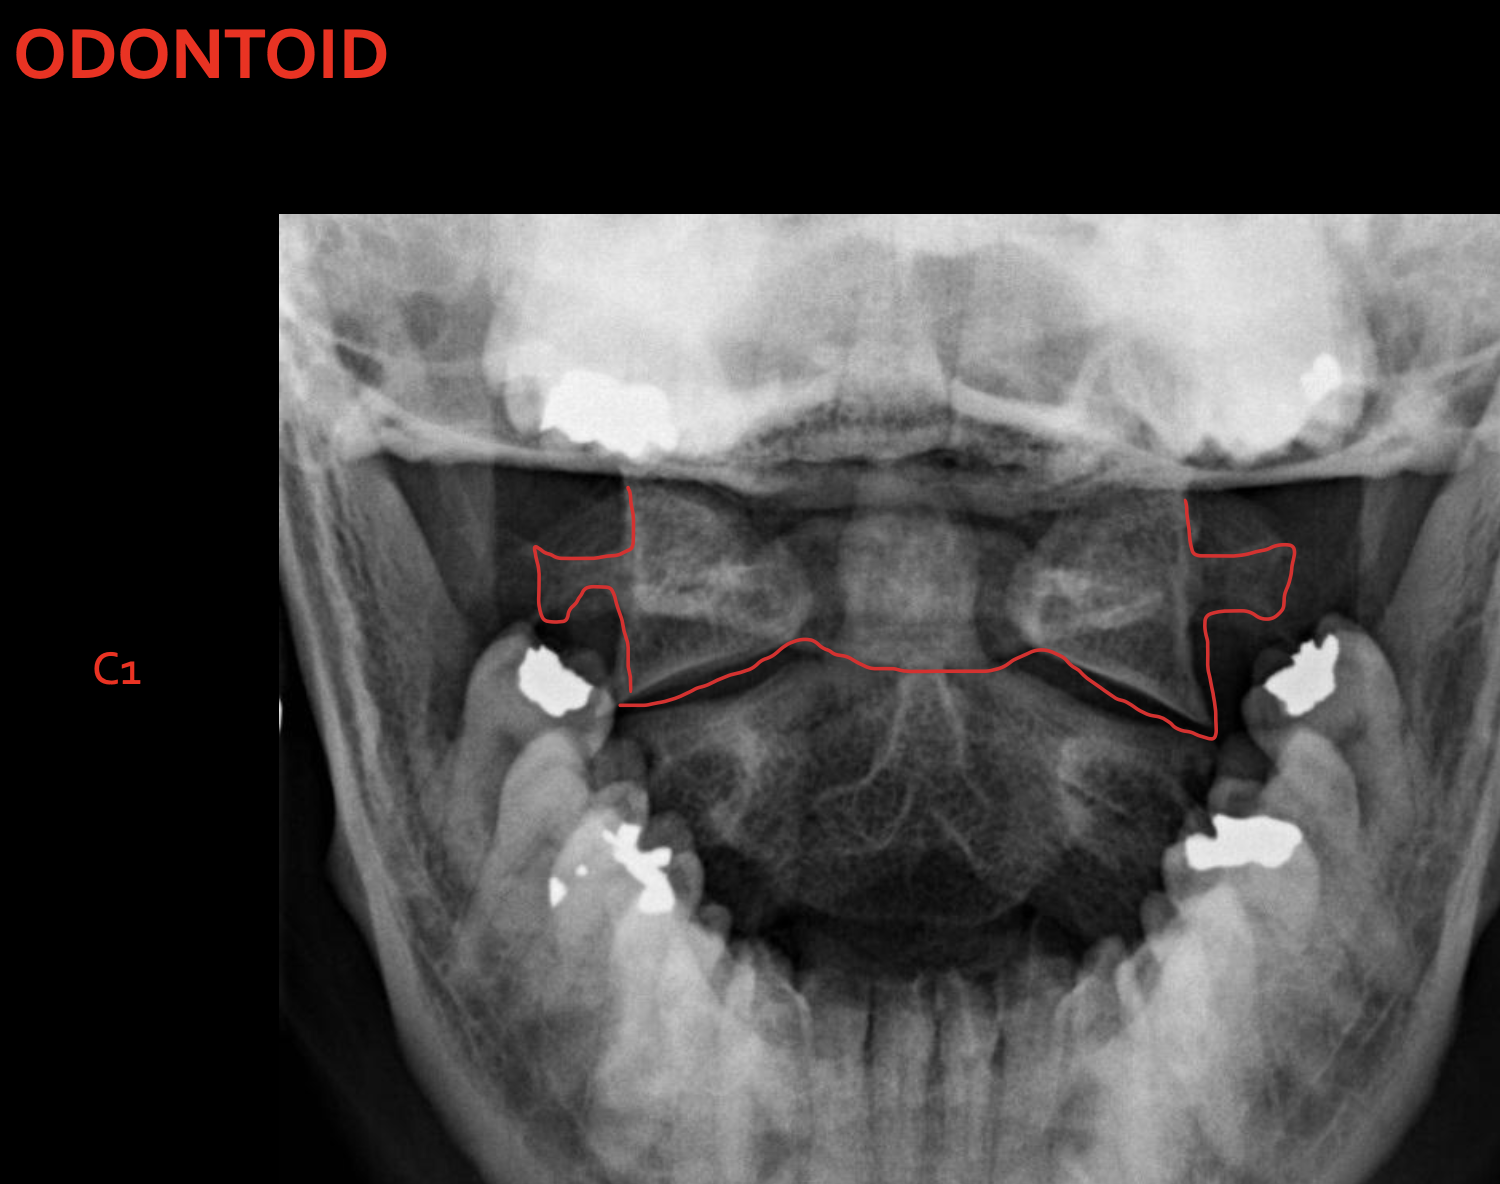

Odontoid process C1

C1 lateral mass

C1